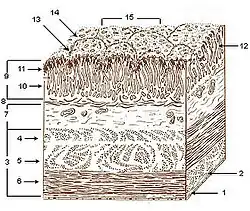

Layers of stomach wall

Layers of stomach wall Gastric acid regulation